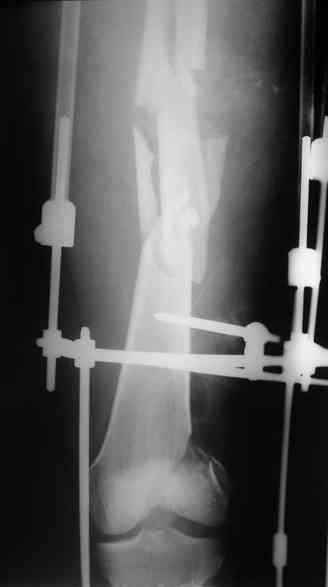

Лучше бы уточнить характер повреждения наружного мыщелка бедра, есть ли его фронтальное раскалывание. Мы бы сделали репозицию мыщелка (если получится, то закрыто) с фиксацией спонгиозными винтами.

Не получится закрыто - наружный парапателлярный доступ, открытая репозиция, винты. И сделали бы закрытый интрамедуллярный остеосинтез бедра антгерадно. Если есть возможность, лучше использовать гвоздь, который позволит провести винты через мыщелок, т.е. очень близко к

дистальному концу.

Вполне возможен и ретроградный остеосинтез бедра, особенно если все-таки придется открывать сустав.

После окончательного заживления раны снять аппарат наложить вытяжение дней на 5-7, посмотреть как ведут себя раны от стержней. Одномоментное снятие аппрата с забиванием гвоздя чревато, сколько, кстати он уже стоит?

Выждав, немного, сделал бы антеградный интрамедуллярный остеосинтез. Насчет того, чтобы винты, фиксирующие мыщелок являлись одновременно блокирующими не согласен - далековато гвоздь забивать придется. Хотя не уверен на 100%